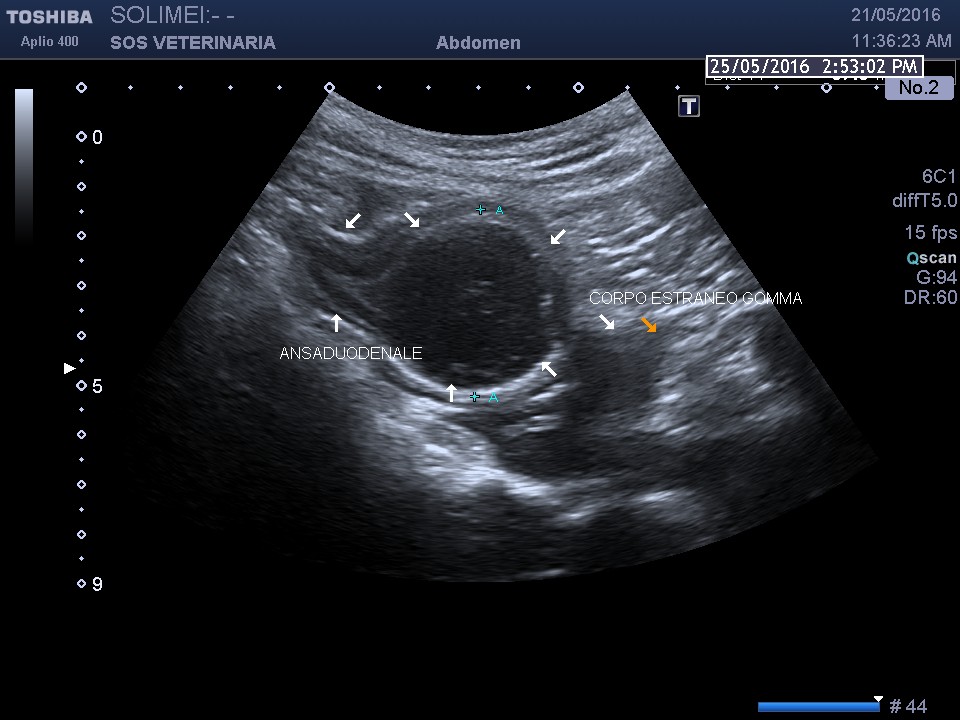

Buldog maschio di 8 anni portato alla visita per emesi incoercibile ,emogas analisi : alcalsosi ipocloremica compatibile con ostruzione alta intestinale ,l’esame ecografico ha permesso di individuare la causa una palla di gomma spugnosa di circa 4 cm la cui peculiarita’ e’ l’assenza totale di sbarramento per l’assorbimento dell’acqua che hanno reso la scansione molto simile ad un ansa intestinale in sezione trasversale .